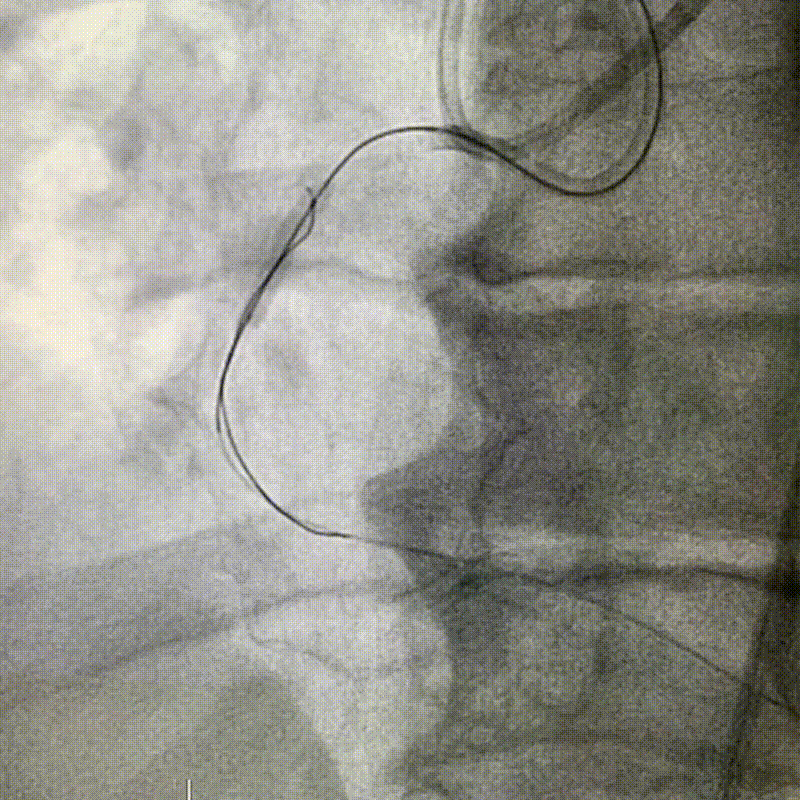

Hoy os compartimos este interesante caso clínico con abordaje anterógrado y retrógrado con el mismo microcatéter Elong™ 1,7 Fr 150cm, realizado en Hospital Universitario Juan Ramón Jiménez.

¡Gracias al Dr. Antonio Gómez Menchero!